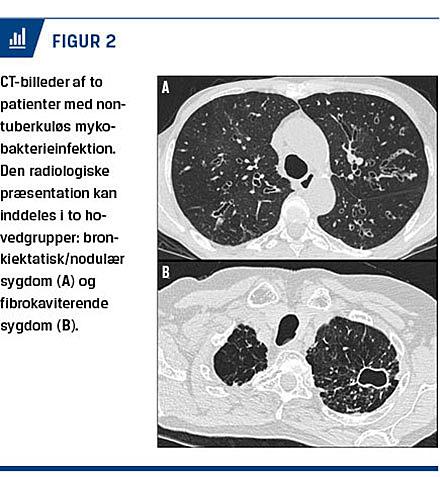

Den radiologiske fremtræden kan på baggrund af CT-resultater inddeles i to hovedgrupper: kaviterende infiltrater eller bronkiektasier og nodulære forandringer (Figur 2). De kaviterende infiltrater kan ikke sikkert skelnes fra lunge-TB [14], selvom man sjældnere ser pleuraeffusion og forstørrede torakale lymfeknuder. Bronkiektasier og nodulære forandringer er den fremherskende radiologiske fremtræden hos mindst 50% af patienterne med M. avium-infektion [15]. Hos ældre kvinder kan der være karakteristiske bronkiektasier og små noduli i højre mellemlap – Lady Windermere syndrome [16], opkaldt efter en figur fra et skuespil af Oscar Wilde. Det formodes, at dette syndrom opstår på grund af suppression af hosterefleksen.